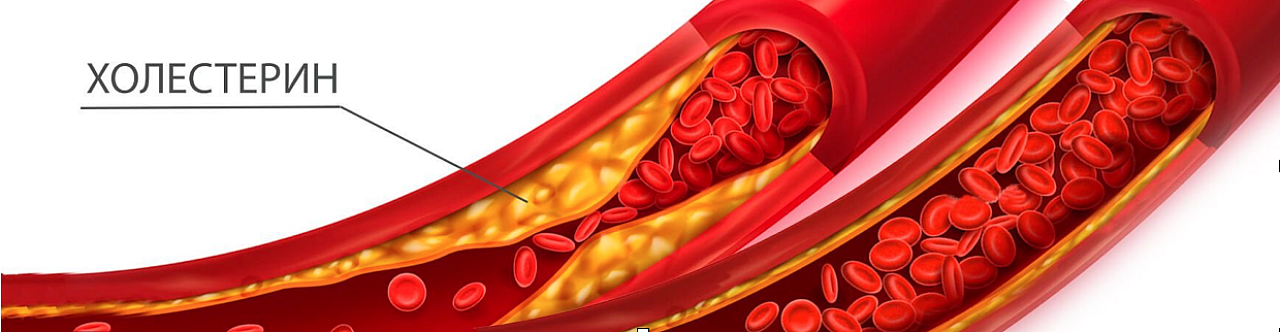

Холестерин в организме: влияние и функции (схемы и диаграммы)